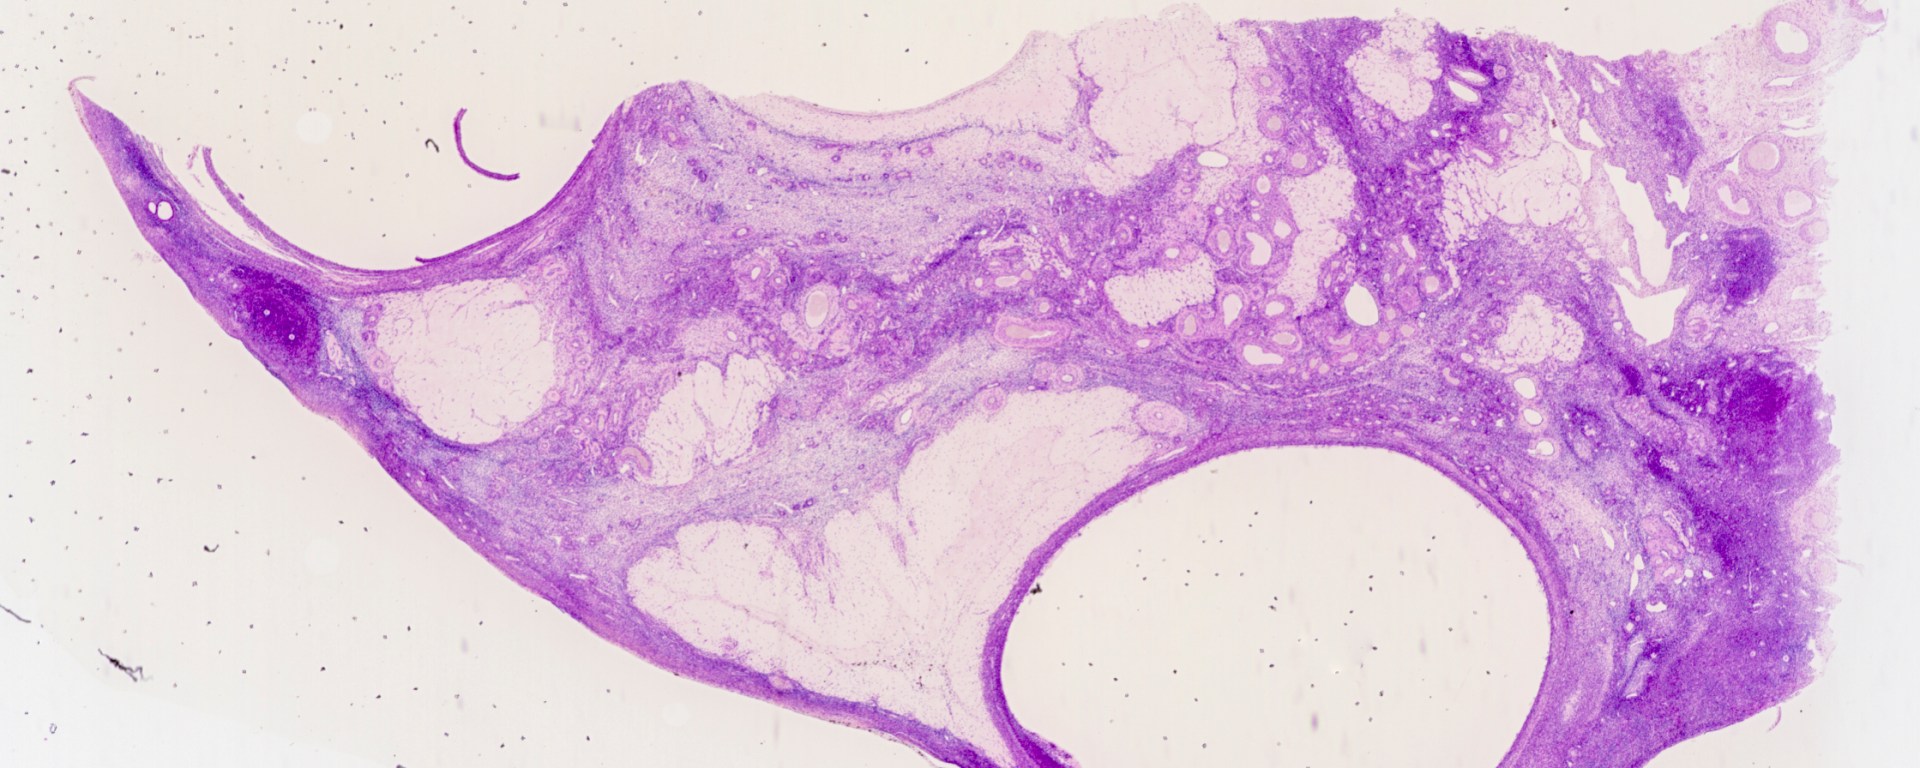

If no implantation occurs or after the placenta is established, the corpus luteum would undergo involution and become a mass of connective tissue known as corpus albicans. Due to the activity of the macrophages, they will eventually become acellular scars, and some will disappear over time. Three of the corpus albicantes are pointed out in this picture. The biggest white-colored structure is an ovarian cyst.